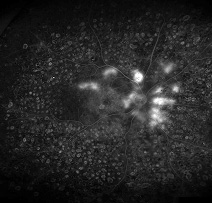

형광안저혈관조영술

당뇨황반부종에 대한 유리체내 주사 전

당뇨황반부종에 대한 유리체내 주사 후